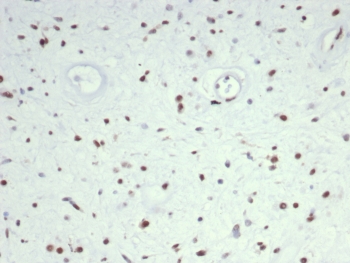

Recognizes a phosphor-protein of 45kDa, identified as MyoD1. The epitope of this mAb maps between amino acid 180-189 in the C-terminal of mouse MyoD1 protein. It does not cross react with myogenin, Myf5, or Myf6. Antibody to MyoD1 labels the nuclei of myoblasts in developing muscle tissues. MyoD1 is not detected in normal adult tissue, but is highly expressed in the tumor cell nuclei of rhabdomyosarcomas. Occasionally nuclear expression of MyoD1 is seen in ectomesenchymoma and a subset of Wilm s tumors. Weak cytoplasmic staining is observed in several non-muscle tissues, including glandular epithelium and also in rhabdomyosarcomas, neuroblastomas, Ewing s sarcomas and alveolar soft part sarcomas.